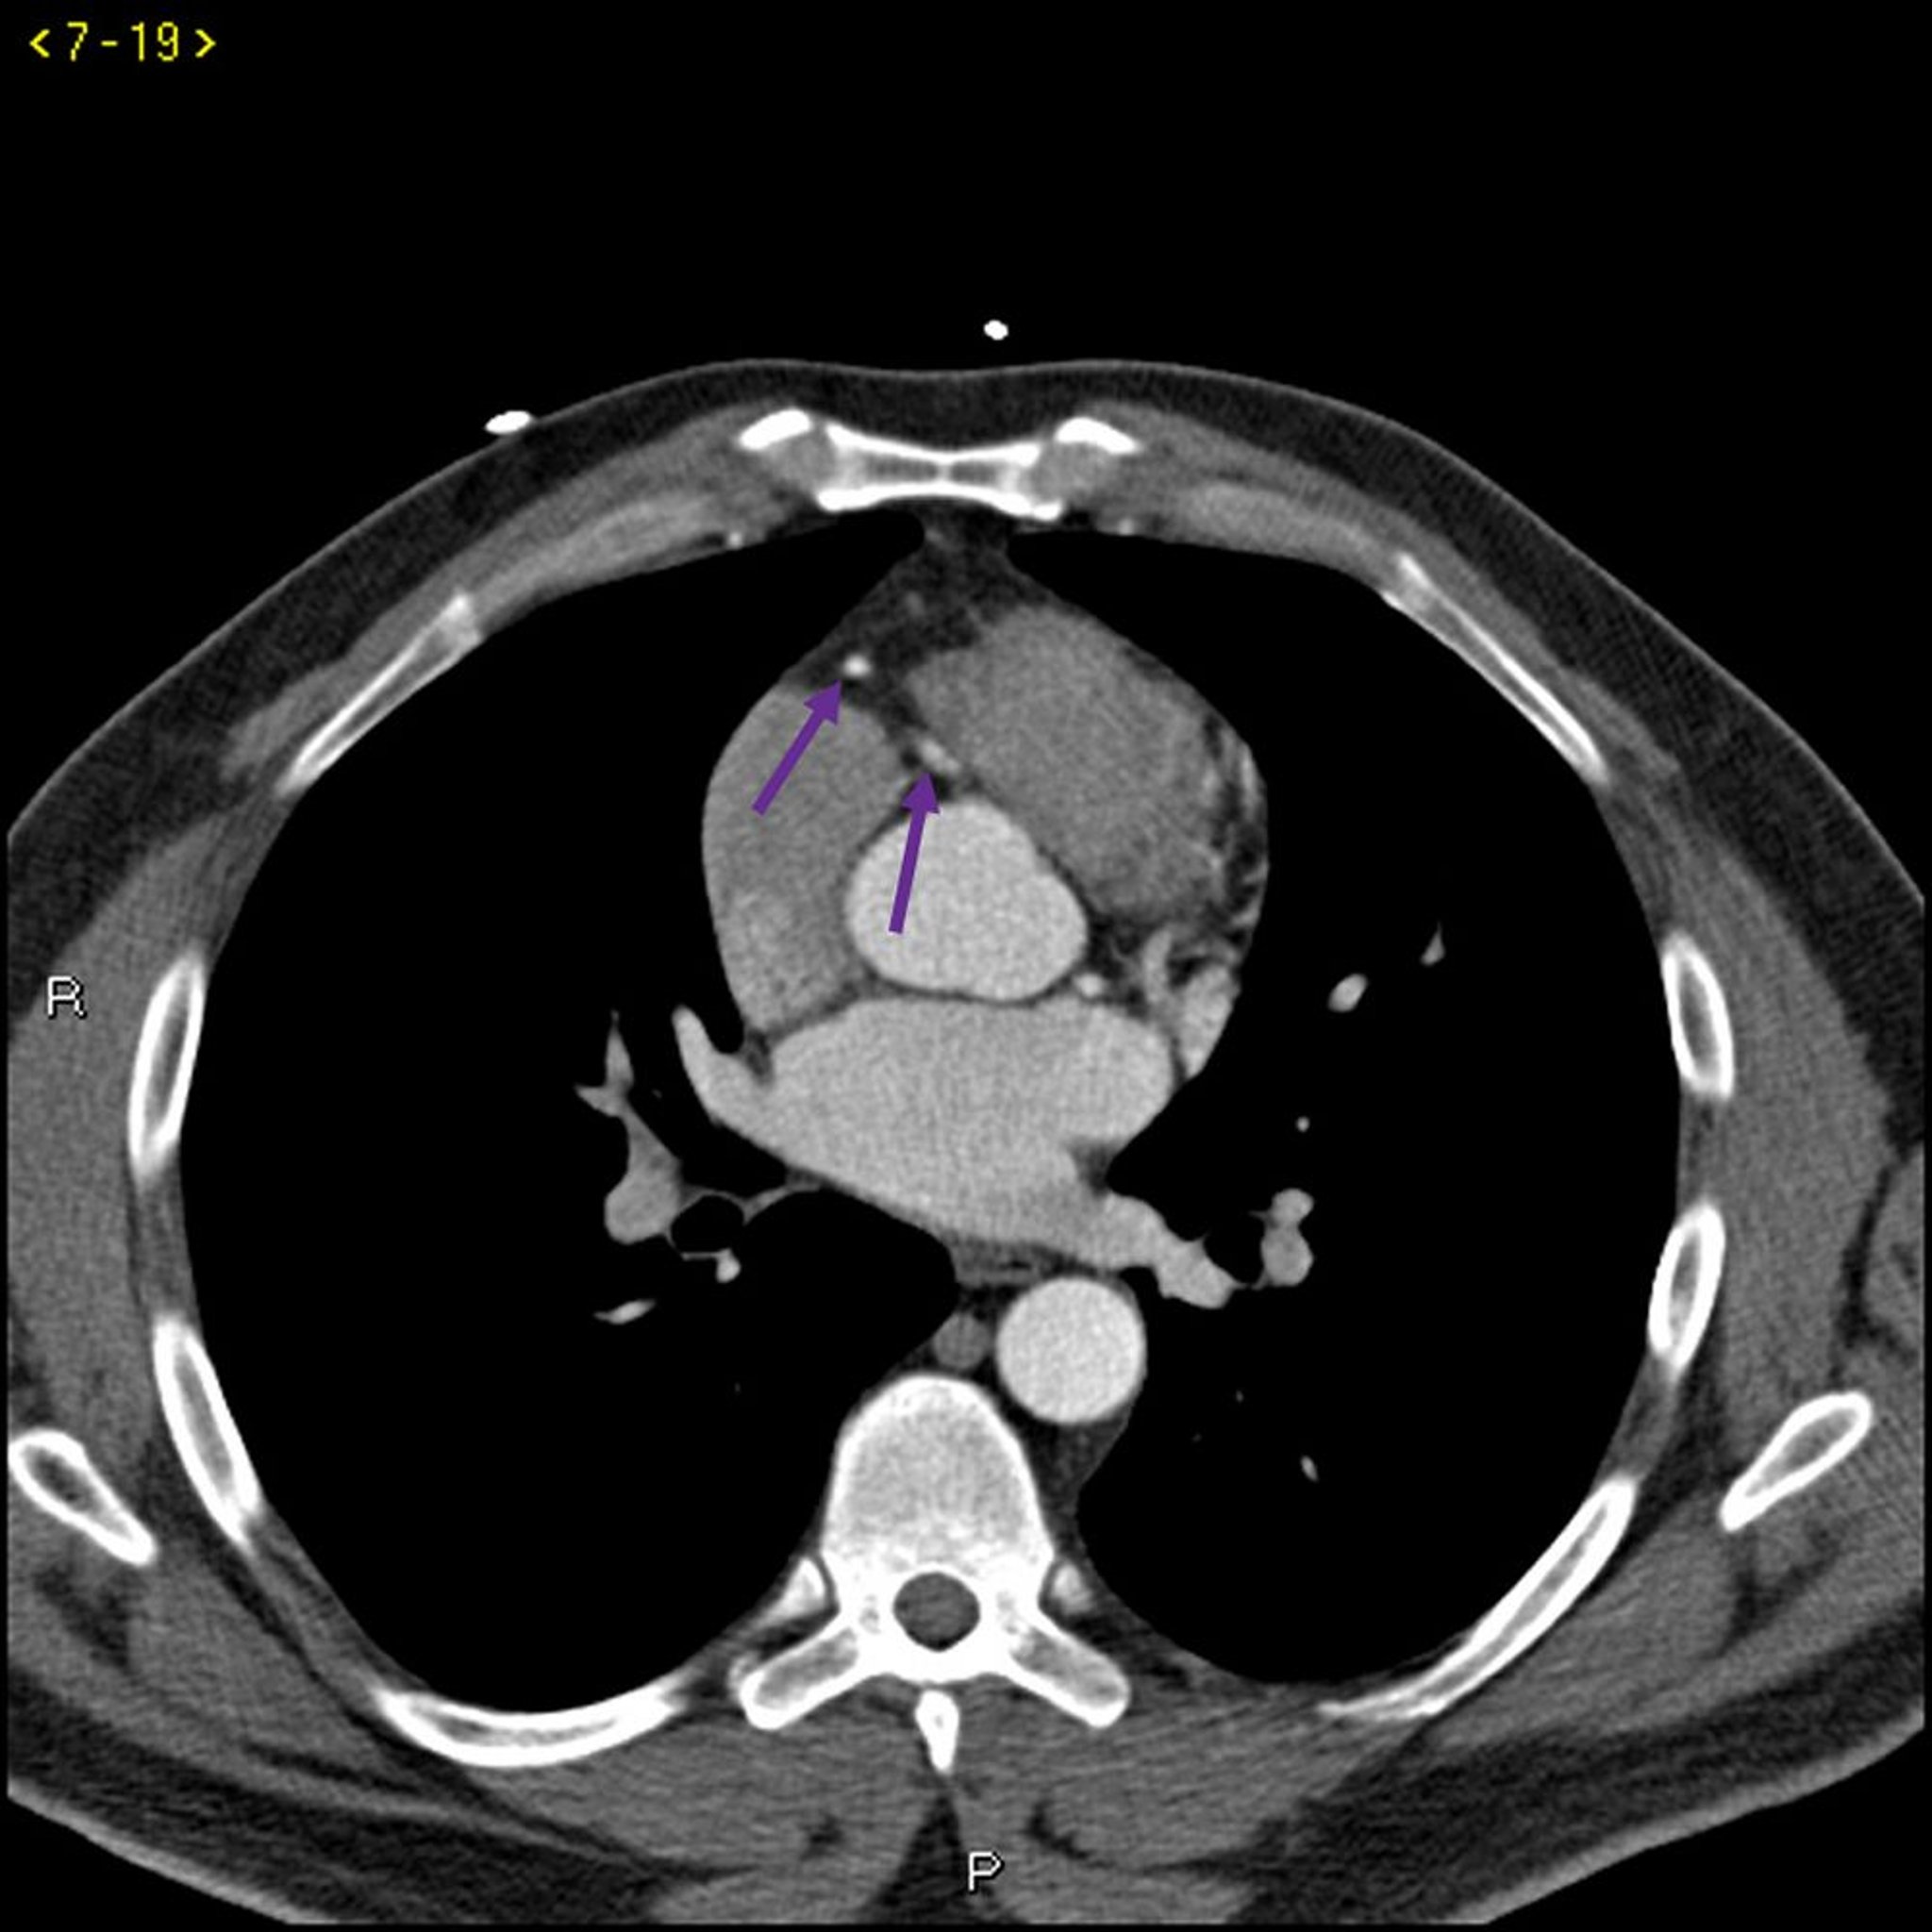

TC com contraste mostrando artérias coronárias normais – Diapositivo 4

Essa TC com contraste mostra artérias coronárias normais. A artéria esquerda principal é indicada pela seta vermelha. As artérias descendente anterior esquerda e circunflexa esquerda são indicadas pelas setas verde e azul, respectivamente, e a artéria coronária direita é indicada pela seta roxa.